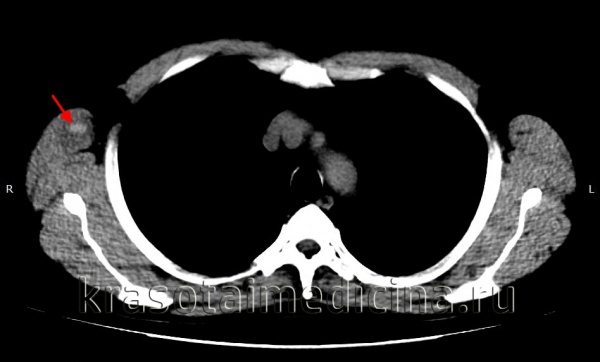

Добавлено: 18.04.2023, 01:56 Источник: Гематома мягких тканей – это полость, образовавшаяся в результате травмы и заполненная кровью или сгустками. Возникает при излитии крови в ткани из поврежденного сосуда. Представляет собой плотное или флуктуирующее опухолевидное образование, болезненное при пальпации, сопровождающееся отеком и изменением цвета кожи. При глубоком расположении проявляется нарушением формы и локальным увеличением объема пораженного участка. Патология диагностируется на основании жалоб, данных анамнеза и внешнего осмотра. В сомнительных случаях назначается ультрасонография. Лечение – местные консервативные мероприятия, в тяжелых случаях показано вскрытие, дренирование. ![]() О заболевании По размерам локальные кровоизлияния могут быть маленькими или обширными. В одних случаях они локализуются поверхностно – в подкожном или подслизистом слое. В других случаях – залегают в толще мышечного слоя или во внутренних полостях организма. Чем большее количество сосудов повреждено, тем тяжелее и обширнее гематома. Симптоматика локального кровоизлияния появляется практически сразу после травматического воздействия. Обычно первыми признаками являются ограниченный отек, интенсивные боли при надавливании и отсутствие флюктуационного симптома. Гематомы чаще всего образуются в местах, подверженных травматизации – голень, затылочная область головы (при падении назад), лицо (прямой удар). Спонтанные гематомы мягких тканей могут иметь разную локализацию и часто являются осложнением более интенсивной антикоагулянтной терапии. Диагностика в большинстве случаев не вызывает сложностей и основана на визуальной оценке поврежденной области. При глубоком залегании гематомы проводится визуализирующая диагностика – ультразвуковая, рентгенологическая или магнитно-резонансная. Лечение в большинстве случаев осуществляется консервативным способом. Хирургическое вмешательство может потребоваться только при больших гематомах с продолжающимся кровотечением. Почему гематома меняет цвет Медики выделяют три отдельные стадии гематомы, через которые она должна пройти, прежде чем полностью исчезнуть. Каждая из них характеризуется определенным цветом кожи, сквозь которую просвечивает кровоизлияние. Появление синяка. Сразу после ушиба мягких тканей ощущается резкая боль, участок кожи в поврежденном месте становится багрово-красным и напухает из-за отека тканей, затем красный цвет постепенно сменяется синим. Красный цвет придают эритроциты, содержащие большое количество гемоглобина. Спустя несколько часов гемоглобин начинает разрушаться, и место ушиба синеет. Из-за отека и воспаления ткани в поврежденном месте повышается температура. Позеленение. Спустя два-три дня отек и температура уменьшаются, состояние тканей более-менее нормализуется, однако сохраняются незначительные болевые ощущения при надавливании. Синий оттенок кожи понемногу переходит в зеленоватый цвет. Пожелтение. Примерно к пятому дню отек полностью проходит, остатки гемоглобина распадаются и выводятся из тканей. Место ушиба становится желтоватым, затем приобретает обычный цвет. Визуальные симптомы гематом наиболее хорошо заметны в случаях, когда излияние крови происходит в подкожном слое. Если же сгусток образуется в более глубоких слоях мягких тканей, то снаружи заметна лишь небольшая, но болезненная припухлость. Такие образования намного более опасны, поскольку процесс протекает незаметно и может сопровождаться осложнениями. Виды повреждений Чем быстрее образуется гематома, тем тяжелее протекает выздоровление. Травмы этого рода подразделяют на: - легкие, развивающиеся в течение суток, сопровождающиеся слабыми болезненными ощущениями и не требующим специального лечения; - средней тяжести, для появления которых требуется не более 5-6 часов, сопровождающиеся заметной припухлостью и болью, ухудшающие двигательную функцию конечности; - тяжелые, образующиеся в течение 2 часов после ушиба, сопровождающиеся нарушением функций конечности, острой болью и заметной припухлостью. Лечение гематом среднего и тяжелого типа должно проводиться под наблюдением врача, чтобы исключить возможные негативные последствия травмы. Кроме тяжести повреждения, существуют и другие критерии классификации гематом: - по глубине расположения – под кожей, под слизистой оболочкой, в толще мышечной ткани, под фасцией и т.д.; - по состоянию разлитой крови – несвернувшиеся (свежие), свернувшиеся и лизированные (заполненные старой кровью, которая не способна к свертыванию); - по характеру распространения крови – диффузные (кровь пропитывает ткань и быстро распространяется), полостные (кровь скапливается в полости между тканями) и осумкованные (с течением времени полость, заполненная кровью, окружается «сумкой» из соединительной ткани); - по состоянию сосуда – пульсирующие (кровь свободно выливается из сосуда и втекает обратно) и непульсирующие (разрыв сосуда быстро запечатывается тромбом). Классификация Систематизация осуществляется по нескольким признакам. Целью деления на группы является оценка тяжести патологии, выбор лечебной тактики, определение необходимости проведения хирургического вмешательства и наиболее вероятного прогноза. В клинической практике различают следующие виды гематом: По локализации. Гематомы могут быть расположены под кожей, в подслизистом слое, под фасцией, в толще мышечной ткани. Наиболее крупные полости локализуются внутри мышц или подфасциально (между мышцей и фасцией), что обусловлено богатым кровоснабжением и эластичностью скелетной мускулатуры. По состоянию сосуда. Пульсирующие гематомы формируются при повреждении сосуда большого калибра, отличаются отсутствием тромба в зоне повреждения, возможностью свободного движения крови из полости образования в полость сосуда и обратно. Непульсирующие гематомы обнаруживаются при нарушении целостности мелких и средних сосудов, дефект стенки которых быстро закрывается тромбом. По состоянию излившейся крови. Несвернувшиеся (свежие) гематомы выявляются в первые часы или дни после травмы, свернувшиеся – спустя несколько суток, лизированные (заполненные старой кровью, неспособной к свертыванию) – через несколько недель. Указанные сроки могут колебаться в зависимости от активности факторов свертывания, размера образования и иных обстоятельств. При проникновении инфекции наблюдается инфицирование, позже – нагноение. По отношению к тканям. При развитии диффузных гематом процесс пропитывания тканей кровью преобладает над процессом их «раздвигания», полость небольшая или отсутствует. При формировании ограниченных образований ткани пропитаны незначительно, основная масса излившейся крови находится в полости. Осумкованные гематомы определяются в отдаленные сроки, характеризуются наличием слоя плотной соединительной ткани, отделяющей полость от окружающих структур. По степени тяжести. Легкие гематомы возникают примерно через сутки после травматического эксцесса, чаще рассасываются самостоятельно. Образования средней тяжести формируются в течение 3-5 часов, требуют проведения консервативных или оперативных мероприятий. Тяжелые повреждения диагностируются через 1-2 часа после травмы, являются показанием для вскрытия и дренирования. ![]() КТ ОГК. Гиперденсное скопление крови в толще мышечного массива грудной стенки справа, окруженное зоной отека. Симптомы Первыми проявлениями патологии становятся боль и местный отек. Характерным отличием гематомы от других травм мягких тканей на ранней стадии является более выраженная ограниченность припухлости, отсутствие постепенного перехода от отечных структур к неизмененным. В последующие часы отек начинает распространяться. Болезненность усиливается, движения ограничиваются из-за боли. Пациенты предъявляют жалобы на ощущение давления или напряжения в пораженной зоне. При поверхностном расположении гематомы кожа становится синюшно-багровой. При глубокой локализации полости может выявляться локальная гиперемия кожных покровов, иногда цвет кожи не изменяется. При пальпации на начальном этапе флуктуация обычно отсутствует, определяется уплотнение и резкая болезненность. После формирования ограниченной полости, содержащей жидкую кровь, выявляется положительный симптом зыбления. Вначале пораженная область при ощупывании напряженная, после спадания отека плотность тканей может снижаться. При благоприятном течении припухлость постепенно уменьшается в размере и исчезает, при неблагоприятном – сохраняется в течение длительного времени, вызывает болезненность при движениях. Диагностика Диагностика осуществляется врачом-травматологом. При отсутствии признаков поражения костей и суставов дополнительные исследования обычно не требуются, диагноз выставляется с учетом данных анамнеза (наличие свежей травмы с характерным механизмом), жалоб больного и результатов физикального обследования. При глубоко расположенных гематомах для оценки тяжести повреждения и дифференцировки с ушибом может назначаться УЗИ мягких тканей. При сопутствующем поражении твердых структур выполняется рентгенография соответствующего сегмента. Кроме ушиба дифференциальную диагностику иногда приходится проводить с переломами, надрывами связок и мышц, реже – с синдромом позиционного сдавления, острым миозитом, ишемией при тромбозе сосуда мелкого или среднего калибра и некоторыми другими состояниями, сопровождающимися плотным локальным отеком. ![]() КТ головного мозга. Гематома периферических мягких тканей левой теменной области Лечение гематомы мягких тканей Лечение обычно осуществляется амбулаторно, тактика определяется тяжестью процесса и временем с момента травмы. При свежих повреждениях конечности придают возвышенное положение, прикладывают холод (грелку с холодной водой, пакеты со льдом, завернутые в полотенце), накладывают давящую повязку для уменьшения кровотечения. После организации небольших образований назначают УВЧ, применяют теплые грелки для ускорения рассасывания. Небольшие поверхностно расположенные гематомы вскрывают в условиях травмпункта. При крупных и глубоких полостях, появлении признаков инфицирования показана госпитализация в травматологическое отделение, вскрытие и дренирование на фоне антибиотикотерапии. При неинфицированных гематомах после вскрытия рекомендовано тугое бинтование для устранения полости и ускорения заживления. Видео про Гематома: откуда берутся ретрохориальные гематомы |